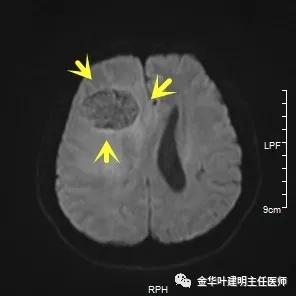

以上图示术前头颅MRI的图像,病灶明显,伴周围显著水肿,中线结构移位。基本可认为是肺癌伴脑转移。那么怎么治疗呢?需不需要手术?能不能手术?手术怎么做?先开颅还是先开肺?